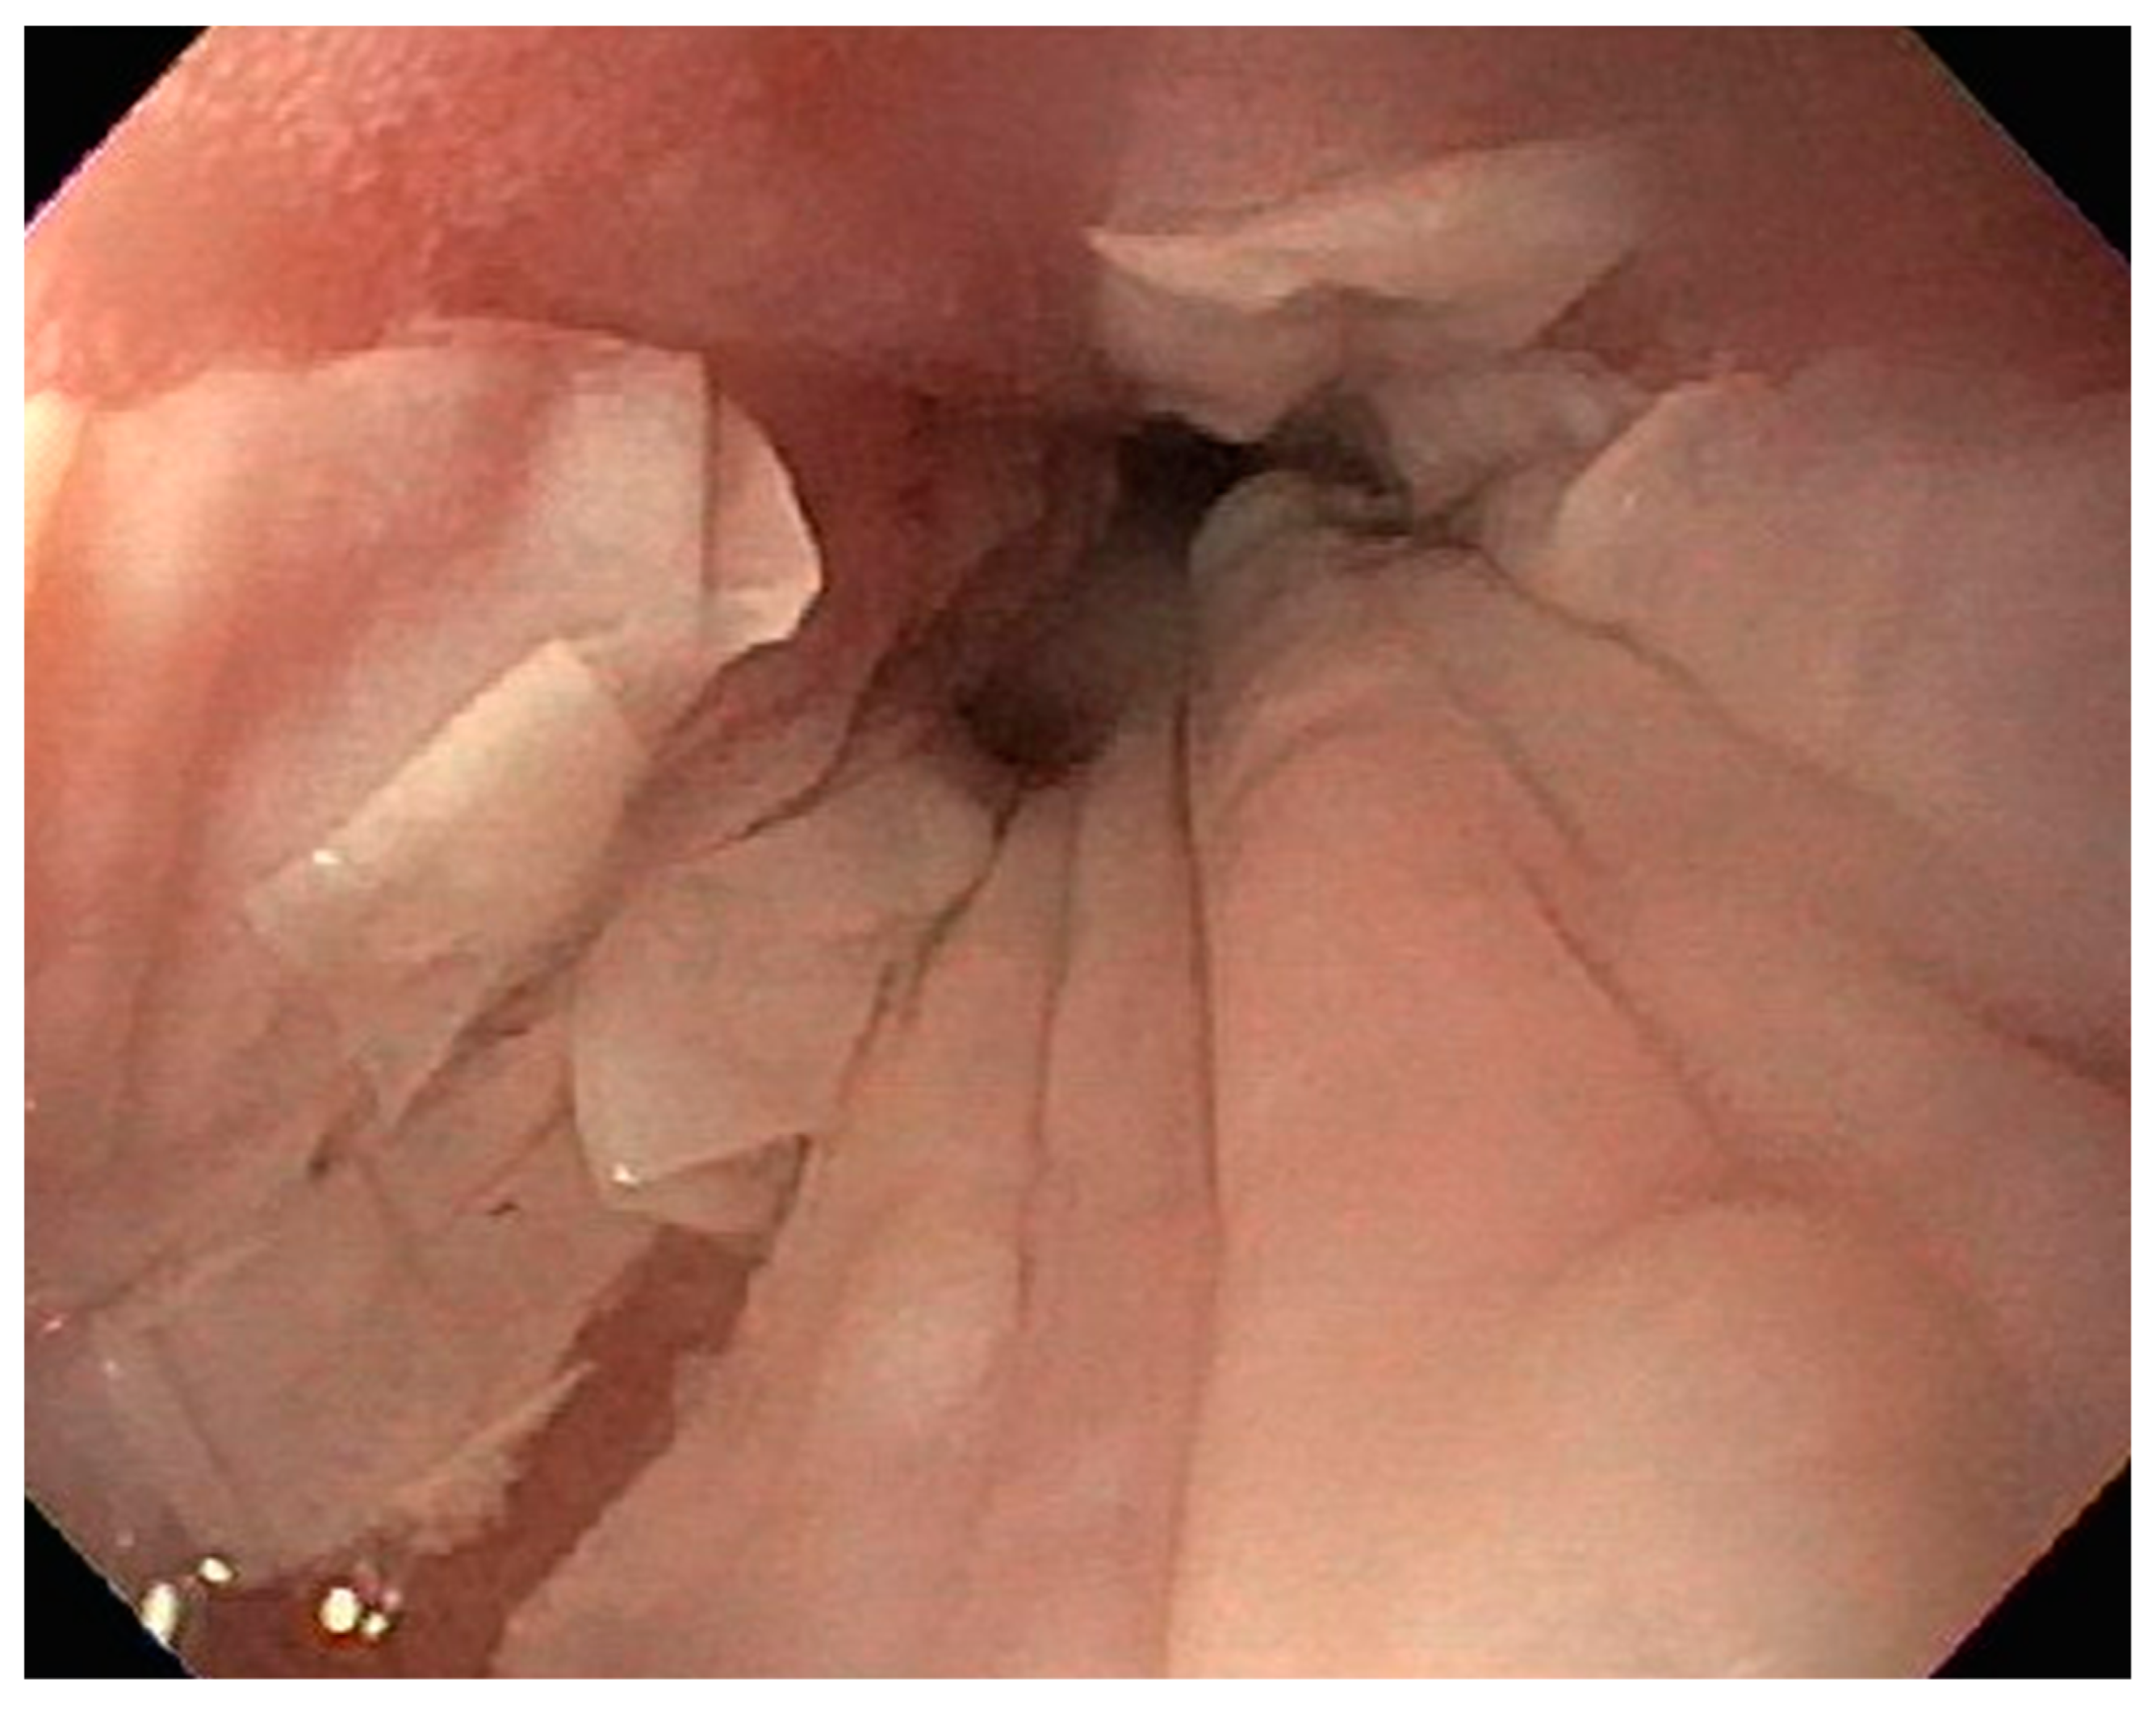

| 1 | F | 66 | Skin | Fundus, cardia, and body | Polypoid lesions with superficial ulcers | Esophagus, duodenum, mediastinum, cervical soft tissue, pancreas | Metastatic malignant melanoma | Radiotherapy and immunotherapy | Comfort care and death 5 days after EGD diagnosis of metastasis |

| 2 | M | 84 | Lymphoid | Fundus and cardia | Ulcerated and necrotic mass | Liver, urinary bladder | Diffuse large B-cell lymphoma | None | Death in 2 months after EGD diagnosis of metastasis |

| 3 | F | 35 | Lung | Fundus | Fungating mass | Esophagus, mediastinum | Large-cell neuroendocrine carcinoma | Chemotherapy-carboplatin/ etoposide | Death 1 month after EGD diagnosis of metastasis |

| 4 | F | 73 | Kidney | Fundus and body | Multiple large friable masses | Liver and lungs | Clear cell renal carcinoma | Nephrectomy, chemotherapy, immunotherapy (Axitinib) | Death 10 days after EGD diagnosis of metastasis |

| 5 | M | 76 | Lung | Body | Cratered ulcers | Liver, bone and adrenals | Small cell carcinoma (poorly differentiated neuroendocrine Ca) | None | Death 7 days after EGD diagnosis of metastasis |

| 6 | M | 61 | Lymphoid | Unknown | Clean based ulcer | None | Marginal zone lymphoma | Rituximab, Zanubrutinib, umbrasilib. OCHOP regimen currently | Progressive disease per latest scans despite therapy |